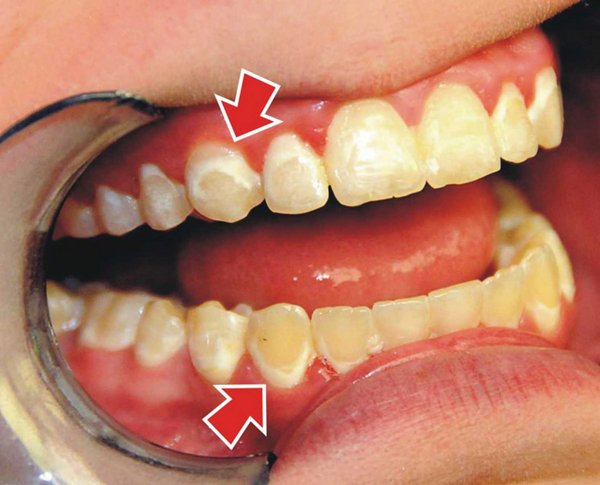

- Thân răng ngắn: Biểu hiện của tình trạng rối loạn mọc răng không hoàn toàn là răng ngắn, nhỏ, vuông, cười hở lợi.

- Cười hở lợi nhẹ: Biểu hiện của trường hợp này là khi cười, mô nướu lộ nhiều hơn 3mm và ít hơn 25% chiều dài của răng.

- Cười hở lợi trung bình: Biểu hiện của trường hợp này là khi cười, mô nướu lộ nhiều hơn 25% và ít hơn 50% chiều dài của răng.

- Cười hở lợi nặng: Biểu hiện của trường hợp này là khi cười, mô nướu lộ nhiều hơn 50% và ít hơn 100% chiều dài của răng.

- Cười hở lợi rất nặng: Biểu hiện của trường hợp này là khi cười, mô nướu lộ nhiều hơn 100% chiều dài của răng.

Phân loại mức độ cười hở lợi